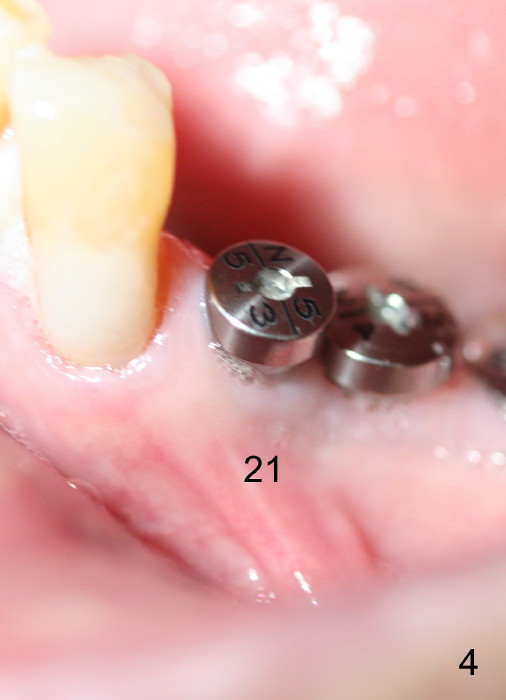

Three weeks post RCT for #22, the patient returns for implant placement at the sites of #19-21 (Fig.1,2). He is asymptomatic. But pain is not well controlled when osteotomy is being done at the site of 21. A shorter and smaller implant (4.1x12 mm, insertion torque <15 Ncm) is placed than planned (4.5x14 mm). One month postop, the implant is not stable at the site of 21 (Fig.3-5). There is a space around the implant, which is continuous with periapical radiolucency (Fig.3 arrowheads). It appears that the immediate implant should have been placed longer following RCT of the neighboring tooth. The tooth #21 has also pre-existing periapical infection.